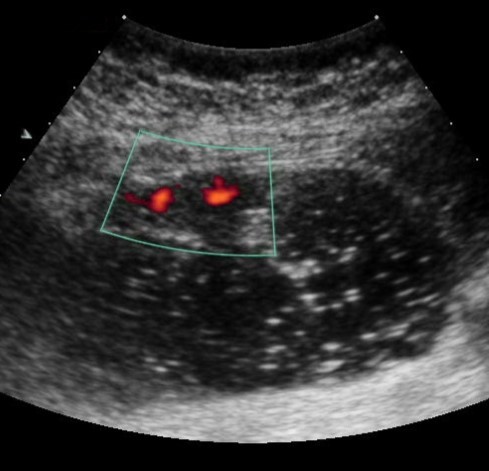

Color Doppler mode was used to assess the nature of the gastric wall lesion in pathologically thickened areas. This method allows the recording of blood flow in the altered areas and using the degree of vascularization to differentiate gastric cancer and other benign changes. Usually in a normal gastric wall it is not possible to visualize the vessels.

Among the 61 patients, pathological vascularization was detected in 42 (68.8%) cases. Of these, all 4 (6.5%) patients with gastric cancer were stage T4 and 38 (62.3%) were stage T3. In 13 cases, vascularization was weak, in 24 cases - moderate, and in 5 cases - enhanced.

Among the 61 patients, pathological vascularization was detected in 42 (68.8%) cases. Of these, all 4 (6.5%) patients with gastric cancer were stage T4 and 38 (62.3%) were stage T3. In 13 cases, vascularization was weak, in 24 cases - moderate, and in 5 cases - enhanced.

Weak vascularization was manifested in the form of a single point color vascular signals, the moderate vascularization - in the form of linear color vascular signals and the enhanced vascularization - in the form of wide color areas inside the tumor (Figure 16, Figure 17).

Figure 16.Distal gastric carcinomas of diffuse infiltrative form of T4 stage. Despite the large size of the tumor the vascularization is manifested in the form of single point color vascular signals.

Figure 17.Gastric carcinomas of infiltrative ulcerative form of Ts stage. Despite the small size of the tumor the vascularization is manifested in the form of wide color areas inside the tumor.